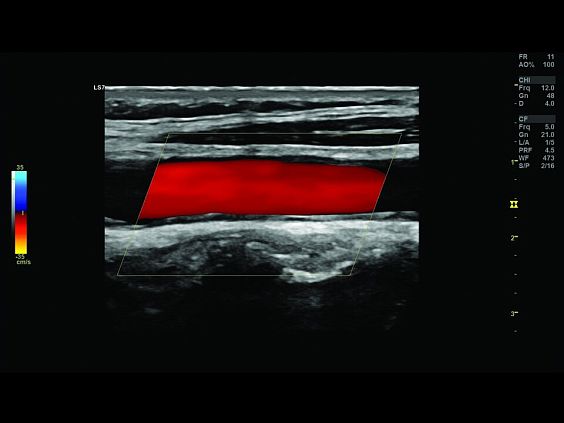

Клинические изображения

- B-Flow / Color B-Flow - режим недопплеровской визуализации кровотока

Ультразвуковой аппарат LOGIQ S7 XDclear предназначен для использования специалистами из различных областей диагностики. Его расширенный функционал включает такие возможности как B-Flow — недопплеровская технология отображения кровотока в B-режиме, компрессионная эластография (качественная и полуколичественная), количественный анализ васкуляризации, функцию В-Steer+ — изменение угла наклона УЗ луча в B-режиме, 3D/4D диагностику и мультимодальную визуализацию.